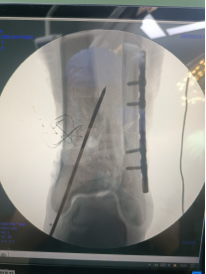

術(shù)中透視脛腓骨遠端,予以克氏針臨時固定。

腓骨予以重建內(nèi)固定板固定。